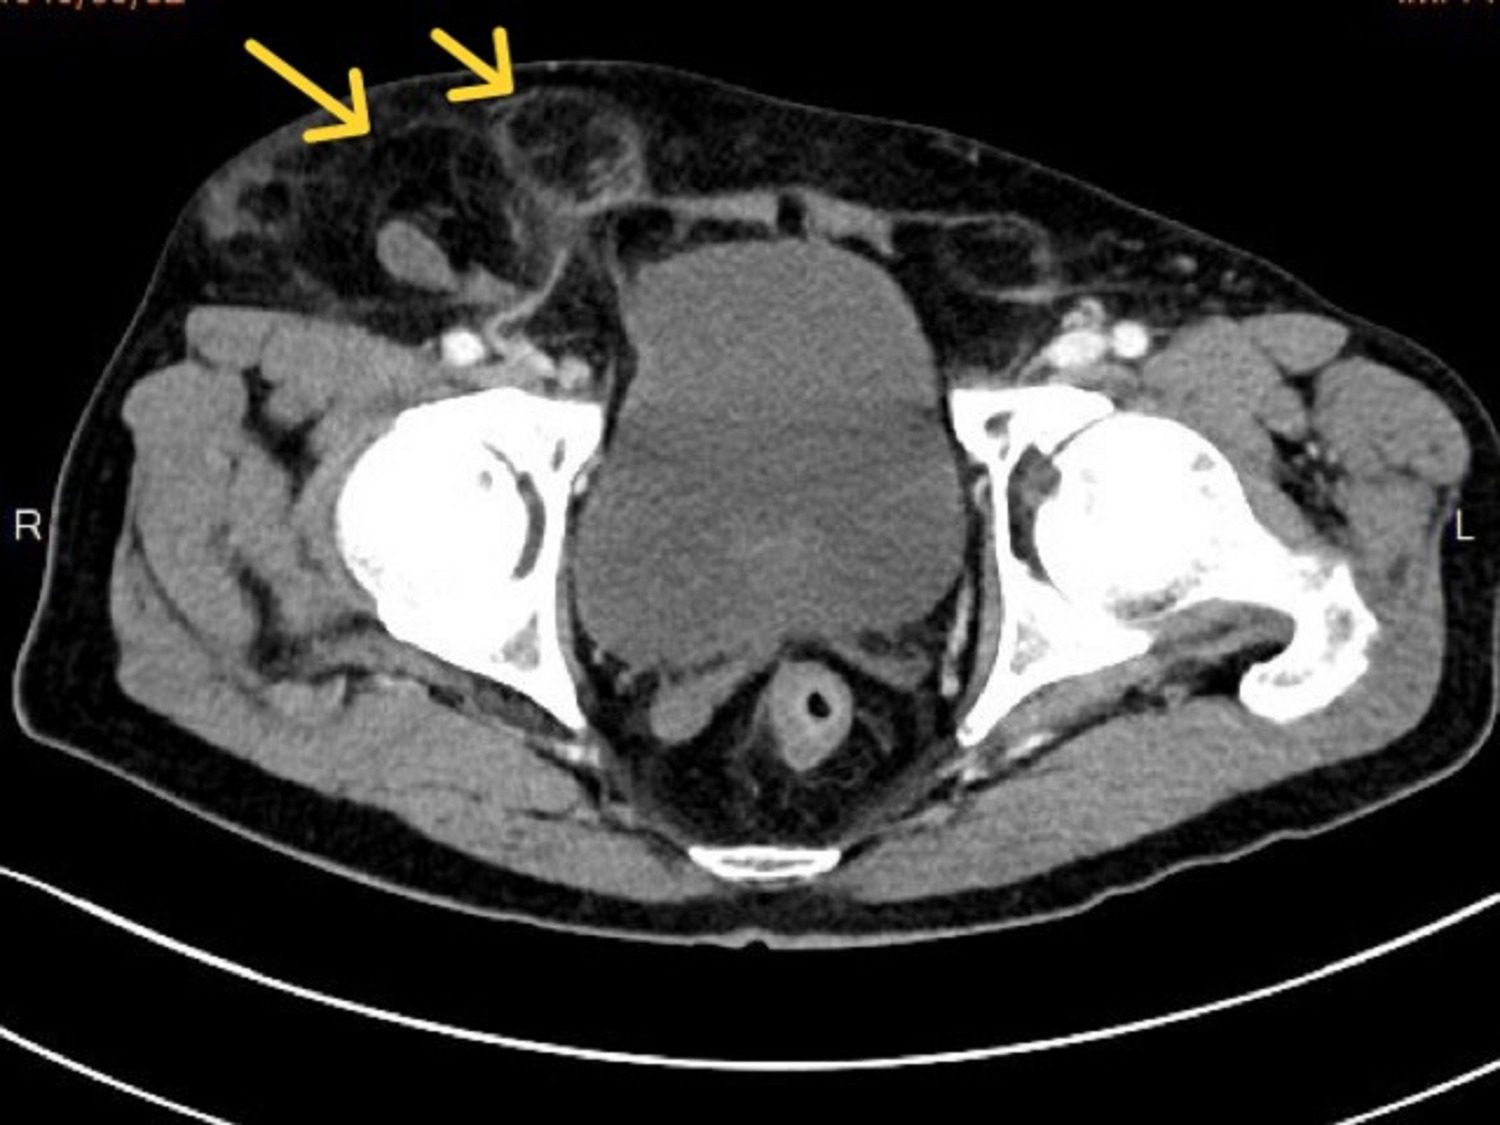

年近八旬的陳伯伯,年輕時因腹股溝疝氣開過兩次傳統手術,近年來經常復發,右下腹靠鼠蹊部位時常「鼓一包」,日前突腹痛難耐就醫,醫師原想徒手幫他復位,但因疝氣造成的突起物實在過於巨大(20*15*10公分),難以一手掌握,影像檢查更發現是罕見的「雙疝氣」,部分小腸及大量網膜組織嵌頓,形成兩個大小不一的疝氣囊,需立即手術以避免腸道壞死。

蘇文隆說,手術過程中,確認病人同時發生股疝氣(femoral hernia)及間接型腹股溝疝氣(inguinal hernia),除將嵌頓的小腸及網膜復位,並使用立體剪裁人工網膜修補疝氣孔,以腹腔鏡縫合腹膜,及切除一小段已壞死的嵌頓小腸,手術歷時七小時終於順利完成。陳伯伯康復出院後回診,疝氣囊已完全消失,右側腹股溝回復平整,總算擺脫「頂著一大包走路」的困擾與不適。